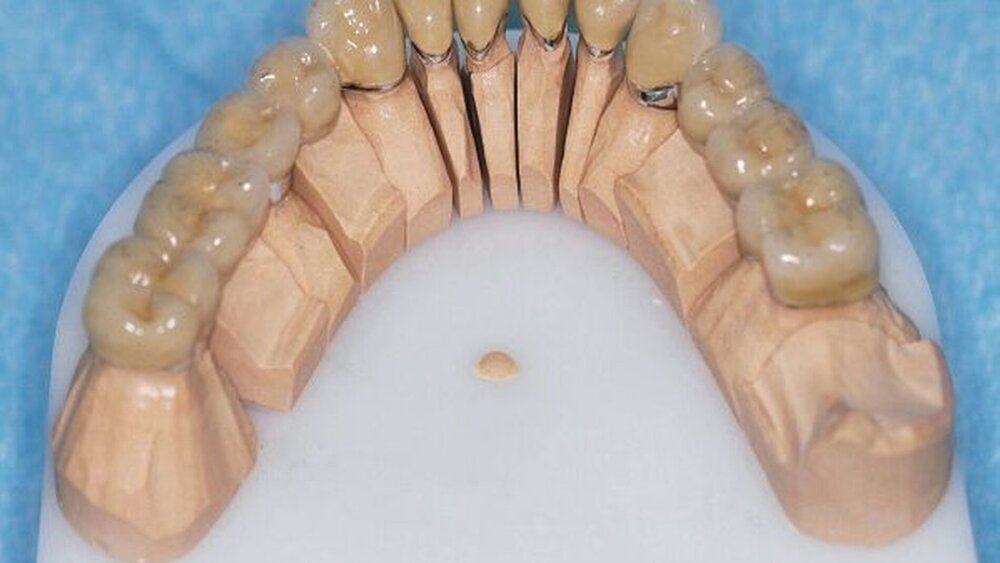

Die Abformungen des OK und des UK erfolgten als Korrekturabformung unter Verwendung eines A-Silikons. Zur Darstellung der subgingival liegenden Präparationsgrenzen wurden mit Adstringentien getränkte, geflochtene Retraktionsfäden in die Sulci aller Zähne eingelegt. Eine adäquate Trocknung der abzuformenden Bereiche wurde durch die Verwendung von Kompressions-Wattekappen, die auf den einzelnen Zähnen platziert wurden, durch Parotispflaster sowie durch eine konstante Absaugung erreicht. Um ein möglichst langes Verarbeitungsintervall zu erzielen, wurde das verwendete Silikon zuvor im Kühlschrank gelagert [Wöstmann et al., 1992; Wöstmann et al., 1999]. Nach erfolgter Abformung wurde ein Gesichtsbogen zur individuellen Übertragung des Oberkiefermodells in den Artikulator angelegt, danach wurden die Provisorien des I- und IV-Quadranten wieder befestigt. Nun wurden partielle interokklusale Registratschlüssel mithilfe eines intraoral anwendbaren Autopolymerisats im Bereich des II- und III-Quadranten angefertigt und beschliffen. In einem zweiten Schritt wurden die Provisorien im I- und IV-Quadranten entfernt und die partiellen interokklusalen Registratschlüssel des II- und III-Quadranten eingesetzt. In dieser Position wurden nun ebenfalls Registratschlüssel im I- und IV-Quadranten angefertigt und beschliffen. Durch dieses Vorgehen war es möglich, die im Rahmen der Registration ermittelte Position – unter Einbeziehung der präparierten Zahnhartsubstanz – auf die Modellsituation des Arbeitsmodells zu übertragen. Abschließend erfolgte die Farbauswahl. Die Arbeitsmodelle wurden mithilfe des zuvor angelegten Gesichtsbogens und der erstellten Registratschlüssel in einen teiljustierbaren Artikulator übertragen. Im Labor erfolgte die Herstellung der Nichtedelmetall-Gerüste der Einzelkronen 22, 32, 31, 41 und 42, die der Brücken 12 bis 21, 35 bis 37 und 43 bis 46 sowie die der Nichtedelmetall- Primärkronen 13, 14, 23 und 24.

In einer weiteren Sitzung erfolgten die Gerüstanproben der angefertigten Restaurationen. Alle Provisorien im Ober- und im Unterkiefer wurden entfernt und die präparierte Zahnhartsubstanz versäubert. Danach wurde die Passgenauigkeit der hergestellten Gerüste am Patienten überprüft. Dies erfolgte unter Verwendung einer Häckchensonde sowie eines niedrigviskösen Silikons. Zudem wurden die mechanische Stabilität, die Friktion und die technische Gestaltung überprüft.

Nach durchgeführter Verblendung und Anfertigung des Sekundärgerüsts der partiellen oberen Prothese sowie Anfertigung einer separaten Wachsaufstellung wurden die Kronen und Brücken erneut anprobiert, um etwaige Änderungen die Farbe der Restaurationen betreffend vor dem Glasurbrand durchführen zu können. Zudem wurde die Sekundärkonstruktion der partiellen oberen Prothese auf ihre Passgenauigkeit hin überprüft. In einem letzten Schritt erfolgte dann die Beurteilung der Okklusion der Wachsaufstellung in Relation zu den angefertigten Kronen und Brücken.